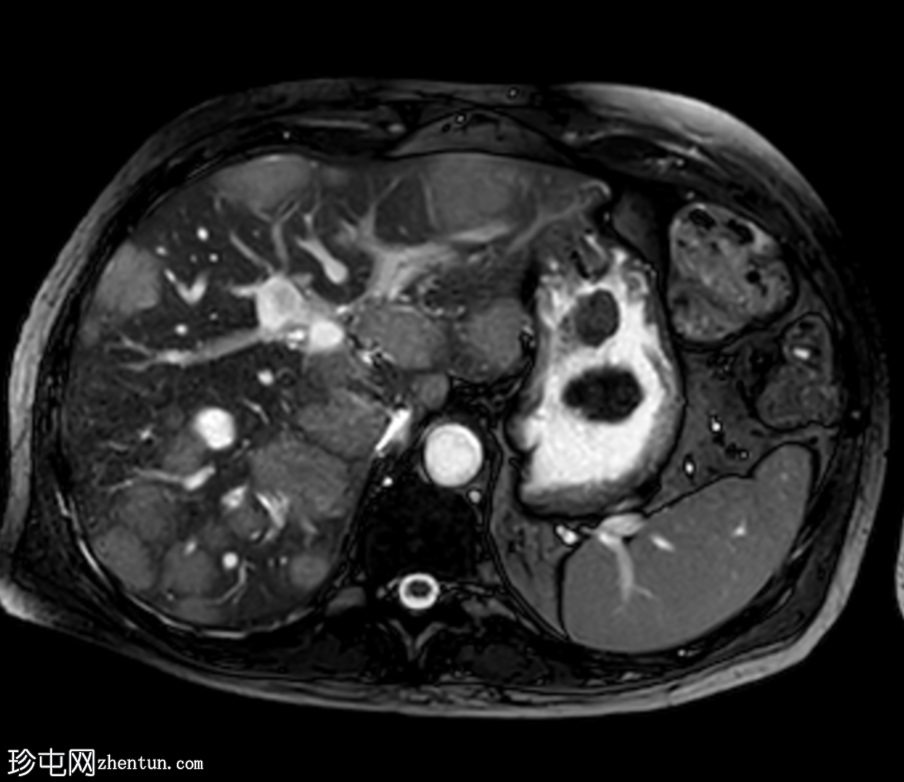

MRI

轴位

T2加权像

肝脏多发病灶,其中数个病灶呈中心T2高信号。

磁共振胰胆管造影(MRCP)显示肝转移灶处存在多处短段胆管狭窄和闭塞,上游胆管扩张,提示

肿瘤

直接压迫/浸润。

肝总管(CHD)和胆总管(CBD)通畅,管径正常。

无胆总管结石。

肝转移灶中心T2高信号最可能是由于肿瘤快速生长导致的中心坏死。

与转移性胆管癌相比,恶性胆道梗阻在胆管癌中更为常见。